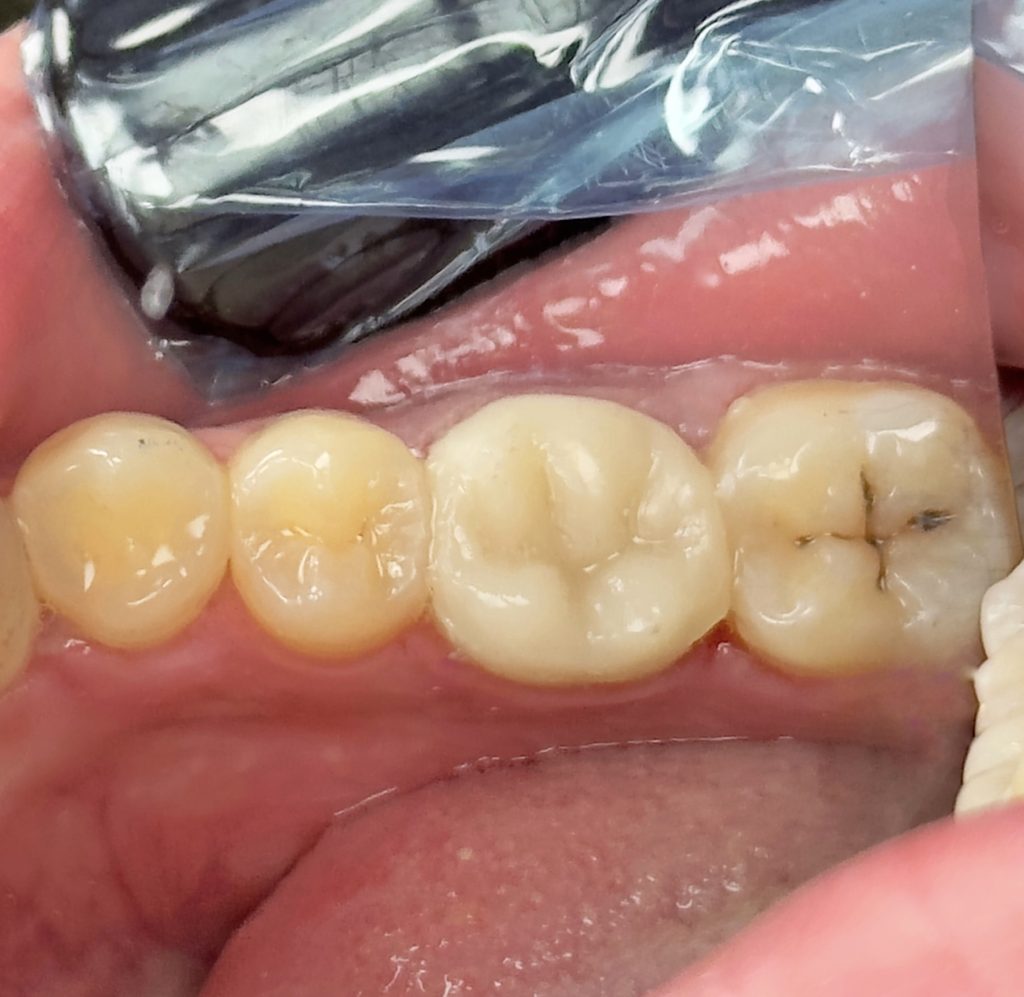

2nd visit :-

-preparation & impression

3rd visit :-

-Air abrasion of both tooth & restoration

-Cementation of the home made indirect composite

-Finishing &polishing